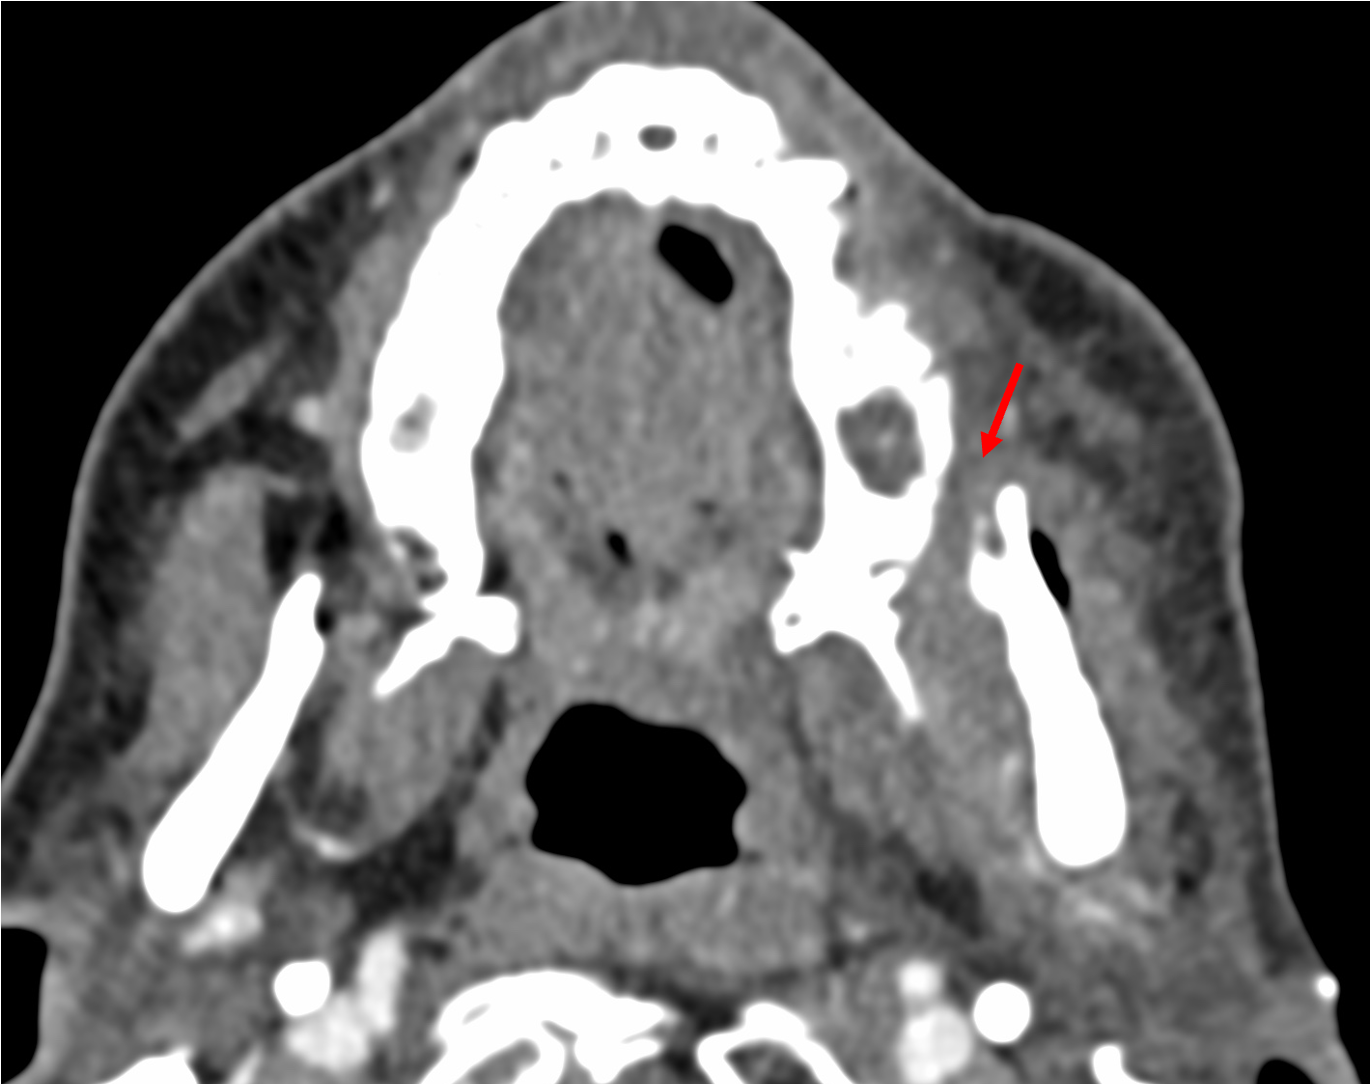

It was decided to follow-up this lesion, since it was not clear, whether this was post-operative of tumor. 6 weeks later, a contrast CT shows minimal increase in the soft tissue

The patient was sent for a biopsy.

How will you biopsy this lesion?